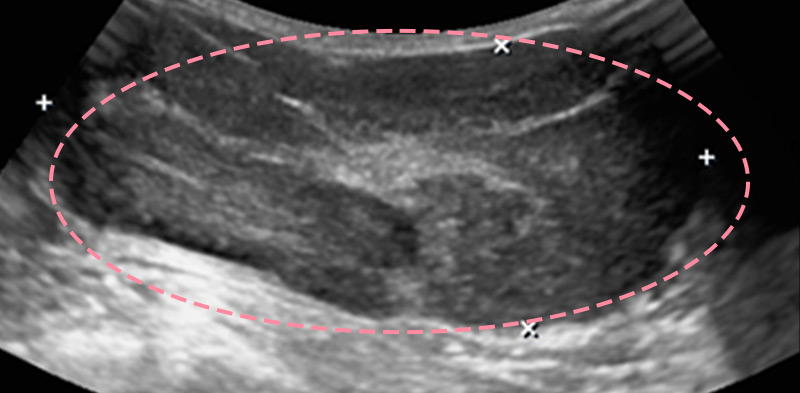

보형물 가슴성형 후 제법 크기가 있는 종양이 발견된 사례입니다.

가슴성형 후 맘모톰시술은 보형물의 위치를 파악하면서 바늘을 다루어야 하기 때문에 고도의 숙련도와 정밀한 판독 능력이 필요합니다.

한송이 원장은 다양한 사례를 접해온 경험과 전문성을 바탕으로 시술을 성공적으로 마쳤습니다.

총조직검사 후 최종 진단 결과 양성 종양(섬유선종)으로 확인되어 맘모톰 시술로 제거를 진행했습니다. 7개월 경과 후 검사를 통해 인공 보형물의 누수 및 파손 없이 깨끗한 내부 상태가 확인되었습니다.